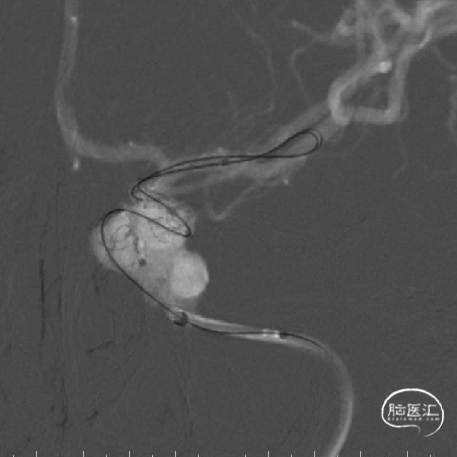

经Fastrack微导管桥接释放3.5mm*35mm及3.5mm*30mmTubridge血流导向密网支架。

术后即刻影像:

术后即刻可见动脉瘤囊内明显造影剂滞留,载瘤动脉通畅,远端分支显影正常,Vaso CT可见支架贴壁良好。

经Fastrack支架微导管桥接释放第三枚Tubridge5.0mm*45mm,“J”型导丝行支架内按摩,使支架充分贴壁,Vaso CT示支架打开良好。

术后即刻造影可见瘤囊内造影剂滞留,载瘤动脉重建良好,远端血流无缺失。